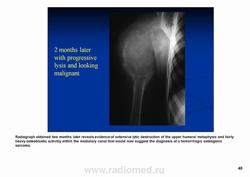

Телеангиэктатическая остеосаркома - редкий (составляет около 4% всех остеосарком) вариант остеосаркомы, характеризующийся наличием кист, заполненных кровью. При рентгенологическом исследовании обычно выявляется полностью литическое поражение без признаков склерозирования, интенсивное вздутие кортикальной пластинки и ее деструкция, часто обнаруживаются периостальная реакция и распространение патологического процесса в мягкие ткани. Гистологическая диагностика телеангиэктатического варианта остеосаркомы может быть относительно несложной при наличии атипичного остеогенеза и высокой степени анаплазии клеточных элементов. Однако довольно часто, особенно у детей и подростков, диагностика вызывает значительные трудности, так как эта остеосаркома, в основном, представлена высокодифференцированным вариантом. Последний отличается тем, что опухолевые клетки определяются только в области выстилки кист и полостей опухоли, злокачественные клетки характеризуются низкой степенью анаплазии, опухолевый остеоид обнаруживается лишь при целенаправленном исследовании серийных срезов, встречаются участки ткани, в которых клеточные элементы и остеоид не имеют признаков атипизма и микроскопическая картина полностью соответствует аневризмальной кисте кости, в связи с чем не исключена диагностическая ошибка при исследовании небольшого количества материала, особенно биопсийного. Относительно медленное развитие опухоли, обычно чисто литическое поражение кости, сходство рентгенологической картины с аневризмальной кистой или гигантоклеточной опухолью кости также способствуют постановке неверного диагноза.

Рентгенологически выявляют метафизарную локализацию, полностью литическое поражение без признаков оссификации, часто интенсивное вздутие кости и её деструкцию, формирование мягкотканого компонента, иногда периостальную реакцию.